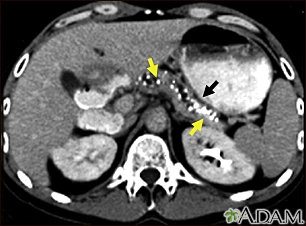

Pancreatitis, chronic - CT scanBackPancreatitis, chronic - CT scanCT scan of the upper abdomen showing multiple white-colored calcifications. These occur in chronic pancreatitis. E-mail FormEmail ResultsName:Email address:Recipients Name:Recipients address:Message: